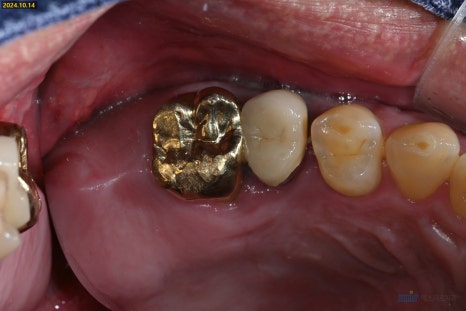

🔹 3. 회복 및 경과

2주 뒤 실밥 제거를 했습니다

이 시기에는 잇몸 주변이 노랗게 보이는 부위가 있을 수 있는데요

많은 환자분들이 "염증이 생긴 건가요?"하고 걱정하시지만

이건 염증이 아니라 잇몸이 회복되는 정상적인 과정입니다

노란빛은 상처 회복 중 생기는 섬유조직이나 백혈구 반응으로,

자연스러운 회복의 일부입니다

윗니 임플란트의 일반적인 기간이 4개월인데

상당량의 뼈이식을 진행한 케이스라

긴 회복기간이 필요했습니다

약 6개월 후 상악의 뼈가 충분히 단단해진 것을 확인하고

임플란트를 완성해드렸습니다

왼쪽 치료 전, 오른쪽 치료 후